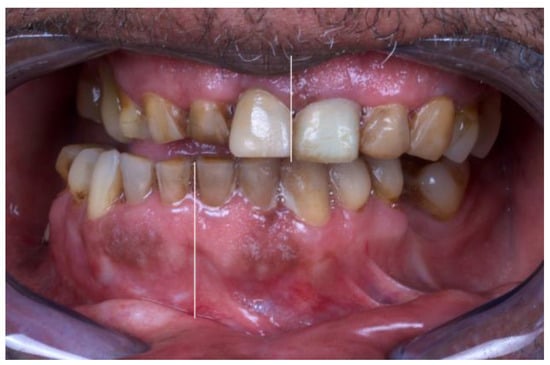

The patient presented with a severe right crossbite (Figure 2), inability to feed due to absence of proper mastication, with a dietary score of <2/10 (liquid scores 0, full diet scores 10), with a recent weight loss of more than 10 kg, achieving 63 kg of weight, with a maximum mouth opening of 24 mm (measured with a certified mouth ruler), and a chief complaint of pain in the temporomandibular area (visual analog scale, VAS, 7/10).

Figure 2. Preoperative occlusion: severe cross-bite with deviation of the interincisal dental midline to the right side.